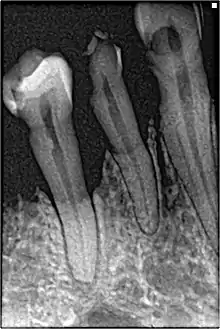

Bone loss in periapical radiograph

2018 Disease Classification of Periodontal Diseases and Conditions breaks down the category of periodontitis into three forms and each of these forms are further broken down into two or more subcategories.[7]